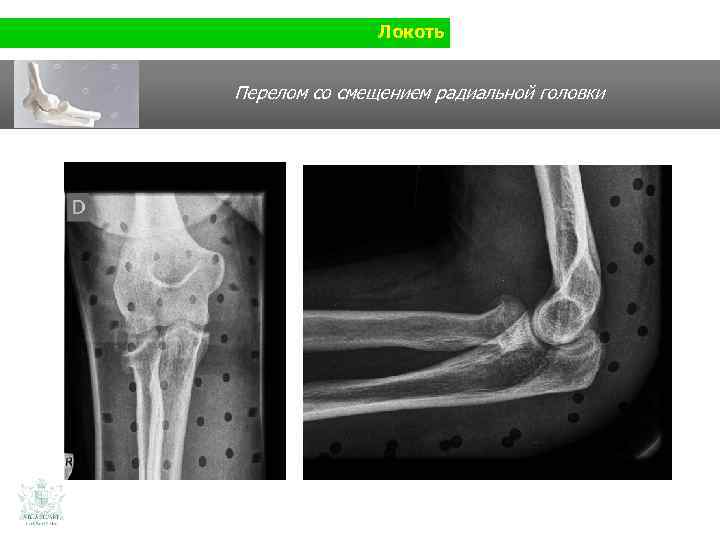

Локоть Клинический случай (локоть) Молодой человек 26 лет Падение на ладонь (при защитной реакции)

Локоть Перелом со смещением радиальной головки

Локоть Перелом со смещением радиальной головки Реконструкция К/Т в 3 D